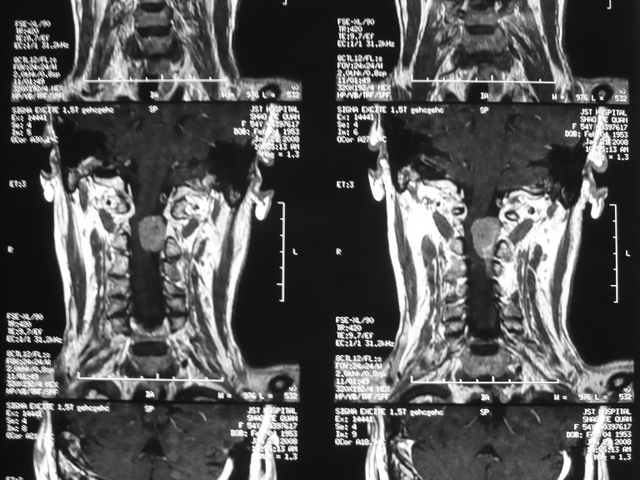

枕大孔区肿瘤

枕大孔区肿瘤枕大孔区肿瘤